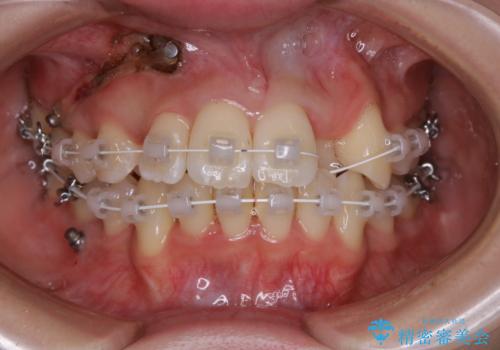

がたつきが強いガチャ歯。埋伏歯抜歯+矯正。すごいところに犬歯が埋まっていたのを抜いてワイヤー矯正治療

- 矯正装置

- ワイヤー矯正 審美装置

- 歯のがたつきを主訴に来院されました。

がたつきの強さから4本抜歯の必要性がありましたが、右上の歯は犬歯が一本埋まっており、乳歯がある状態でした。

右上については先に乳歯を抜歯して、犬歯が使えるようであれば第一小臼歯を抜歯することとして治療を開始しました。

当初、犬歯が動くようであれば代わりに小臼歯を抜歯する予定でしたが、

開窓して器具で力をかけても動く様子がなかったため抜歯とし、小臼歯を犬歯に見立てて治療を完了しました。

結果的に見た目の違和感もなく、期間の短縮にもつながりました。